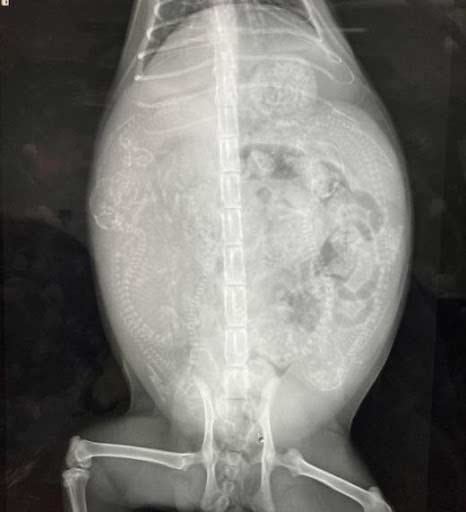

実際のレントゲン写真